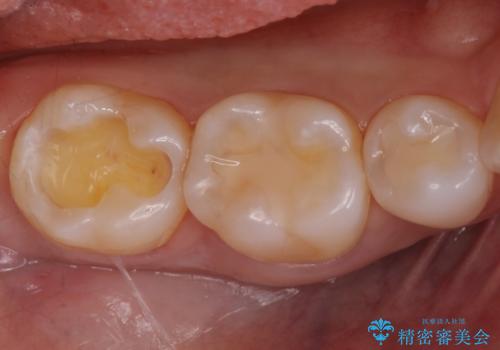

奥歯が欠けた セラミックインレーでの修復後、ナイトガード装着

- 右下の奥歯が欠けたとのことで来院されました。

欠けた部分にはセラミックインレーで修復処置を行い、今後の破折リスクを抑えるためにナイトガードを製作していきます。